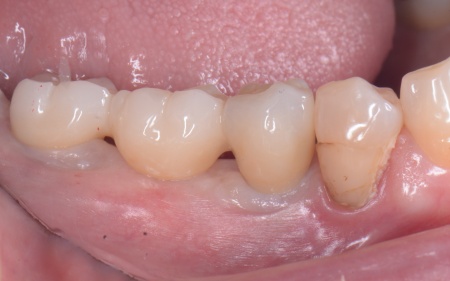

①入れ歯 ②インプラント それぞれのメリットとデメリットをお伝えしたところ、患者様は「できるだけ違和感がなく噛めるようになりたい。またなるべく短期間で治療を終えたい」と希望されたため、抜歯と同時にインプラントを埋め込む抜歯即時埋入法を提案し、同意いただきました。 まず、右下奥歯(第2小臼歯、第1大臼歯)を抜きます。 抜歯後にできた穴とインプラントの間には隙間が生じるため、骨の再生を助ける目的で骨補填材を使用しながら、丁寧に縫合しました。 3ヶ月後、インプラントと骨がしっかりと結合したことが確認できたため、被せ物を作製するための型取りを行います。 後日、完成した被せ物を装着し、見た目や噛み合わせに問題がないことを確認して、治療を終了しています。 |